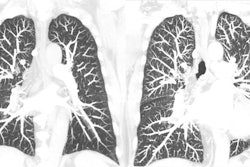

- How PCCT is set to revolutionize cardiovascular and thoracic imaging